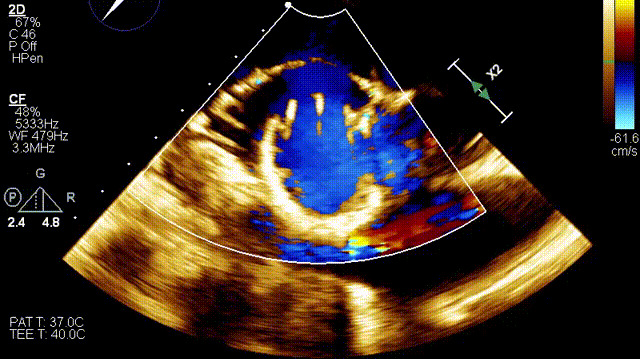

術(shù)后超聲

手術(shù)在全麻狀態(tài)下開展,此次手術(shù)采用經(jīng)右側(cè)頸靜脈入路的方式將輸送器送入患者心臟內(nèi),在TEE及DSA引導(dǎo)下調(diào)整輸送器頭端角度,使得輸送器與三尖瓣瓣環(huán)平面垂直。在輸送器進(jìn)入右心室后釋放室間隔錨定裝置,而后釋放瓣葉夾持件(2個(gè)耳片結(jié)構(gòu))成垂直狀態(tài)。在TEE及DSA確定夾持件固定至三尖瓣葉根部且位于右室側(cè)后釋放人工瓣心房側(cè)盤片。隨后調(diào)整瓣膜同軸性以及室間隔錨定件位置(貼合室間隔),前推藏針管并固定,進(jìn)而釋放室間隔錨定裝置,并再次確認(rèn)瓣膜位置、穩(wěn)定性及同軸性,合攏輸送鞘后撤出輸送器,完成LuX-Valve Plus人工三尖瓣瓣膜的植入。